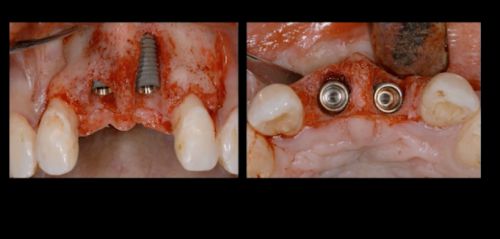

Фото. Внедрены 2 имплантата в области 11, 21 зубов.

Фото. Фиксированы трансферы для снятия оттисков и изготовления временных реставраций.